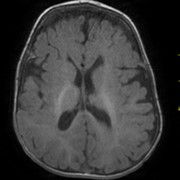

En las ecografías fetales destacaba un CIR tipo I y la presencia de una ventriculomegalia derecha. Las serologías maternas (VIH; VHB; VHC; lúes, toxoplasma)  fueron negativas y rubéola inmune. El parto fue mediante cesárea urgente por estado fetal no tranquilizador a las 34+5 semanas, tras presentación cefálica. Nació con un peso de 1680 g(p4;-1.8DE), longitud 42 (p4;-1.8DE) cm y perímetro craneal 28,5 cm(p4;-2.04DE).  Prueba de Apgar: 6 y 8 al minuto y cinco minutos de vida, respectivamente con un pHau de 7,22. Destaca en el examen neurológico una hipotonía central y llanto agudo. Examen dismorfológico ( Fig. 1A y B) y RM cerebral ( Fig 1C).

Nuestra paciente presenta una cara plana y redondeada,  hipertelorismo, micro-retrognatia y exotropia izquierda. En la RM  se aprecia un adelgazamiento importante del CC y una prominencia llamativa del espacio extraxial. A la exploración destaca una marcada hipotonía y déficit de atención, seguimiento visual y sonoro. Todo ello asociado a una marcada microcefalia, talla baja, con un llanto con un tono particularmente elevado. Destacaba un marcado reflujo gastroesofágico y dificultades en la alimentación, y finalmente requirió un botón gástrico.

Figura 1C. RM cerebral. Corte axial-T2-WI.